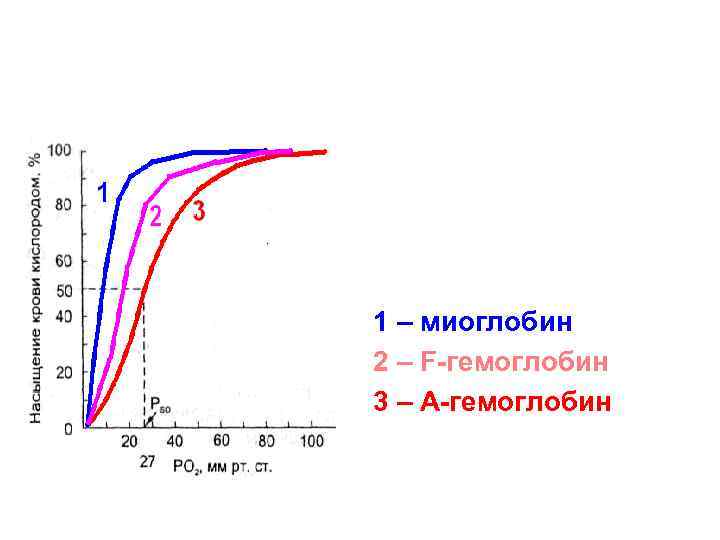

1 – миоглобин 2 – F-гемоглобин 3 – А-гемоглобин

1 – миоглобин 2 – F-гемоглобин 3 – А-гемоглобин